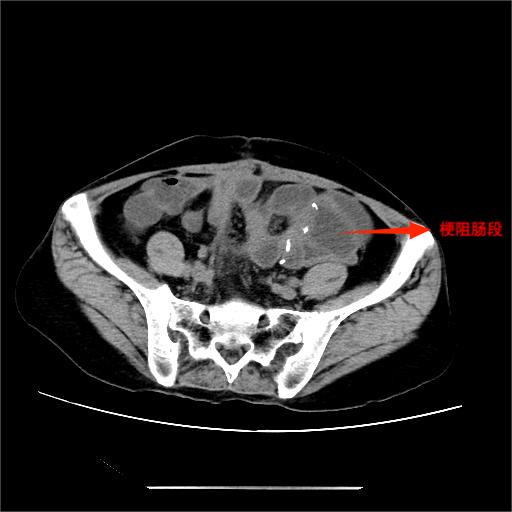

▲腹部CT所见

入院后,完善相关检查,腹部立位平片提示肠管扩张,可见多个液气平面,结合病史考虑术后肠梗阻。经综合评估,决定先行保守治疗,在胃肠外科和疝外科刘奇副主任医师团队协作下,为患者置入肠梗阻导管。置管后,患者腹胀、腹痛症状明显缓解,胃肠减压引流通畅,肠鸣音逐渐恢复。经精心护理及营养支持,患者肛门排气排便恢复正常,复查腹部平片示肠管扩张较前明显改善,无液气平面。病情持续好转,顺利出院。